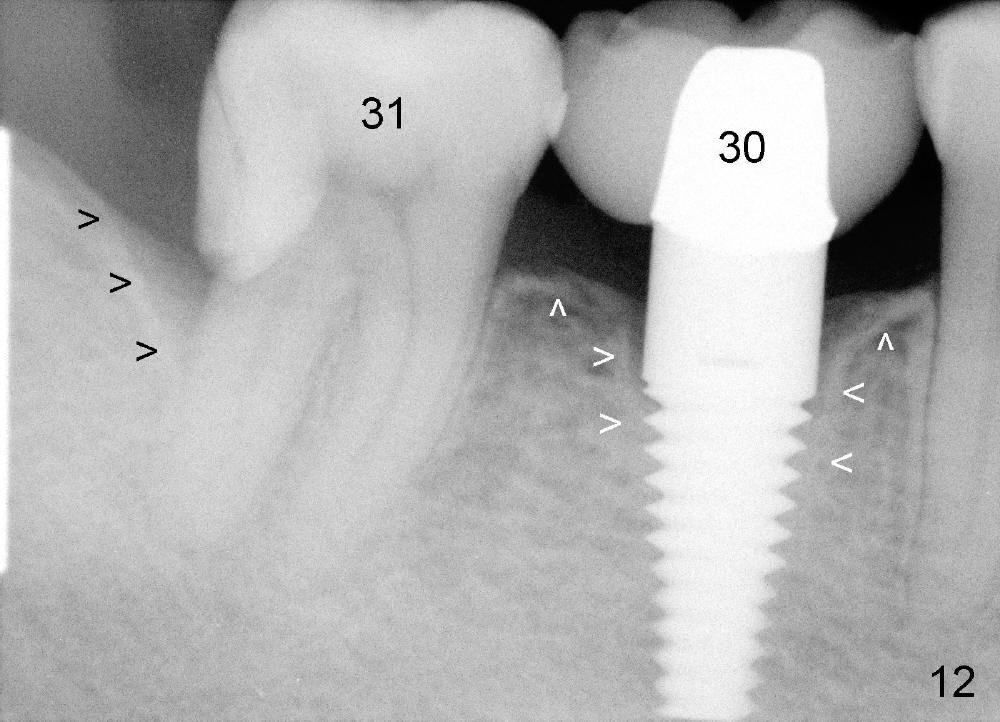

Fig.12-16 are taken 9 months after the orthodontic treatment. The lamina dura appears to form mesial and distal to the implant at the site of #30 (white arrowheads). There is no gross bone resorption associated with orthodontically moved teeth (Fig.12,13: #2,3,31). The posterior overjet remains normal (Fig.14). The arrowheads in Fig.15 indicate a worn facet, which was caused by the previous abnormal overjet (Fig.2). The alignment of the upper right quadrant also remains normal. The patient wears suction down retainers. He is pleased with improvement of mastication.

While the bone continues growing around the implant 1.5 years postop (Fig.17, as compared to Fig.12), the tooth #31 loses composite distally (*). A Zirconia onlay is cemented 1 year 10 months post implantation (Fig.18 arrowheads); the posterior interdigitation remains normal (Fig.19).